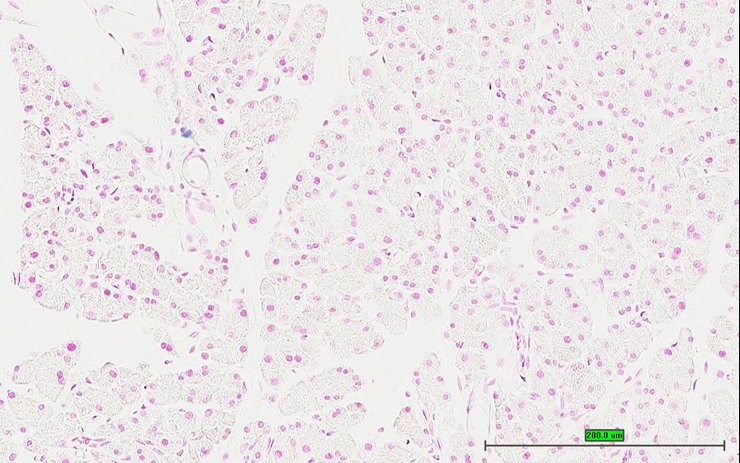

TS28: pancreas Present UC Davis_1876100

Specimen UC Davis_1876101: postnatal adult; Kcna1tm1.1(KOMP)Vlcg/Kcna1+ (more )

TS28: pancreas Present UC Davis_1876031

Specimen UC Davis_1876032: postnatal adult; Kcna1tm1.1(KOMP)Vlcg/Kcna1+ (more )

Structure Level Pattern Image Note

TS28: pancreas Present UC Davis_1876032

Specimen UC Davis_1876033: postnatal adult; Kcna1tm1.1(KOMP)Vlcg/Kcna1+ (more )

TS28: pancreas Present UC Davis_1876033

Specimen UC Davis_1876034: postnatal adult; Kcna1tm1.1(KOMP)Vlcg/Kcna1+ (more )

TS28: pancreas Present UC Davis_1876034